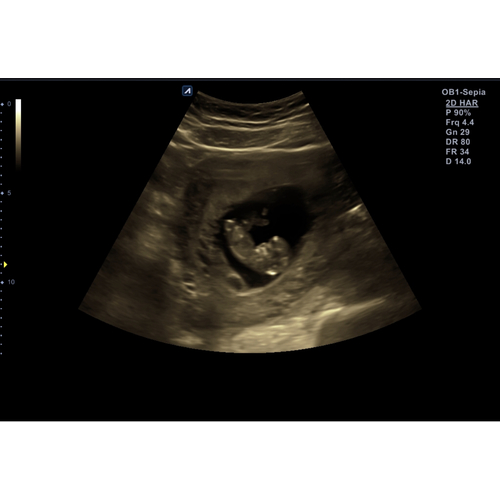

Is hier iets te zien?

Is dit een echo van minimaal 12w..?

Het lijkt van eerder..